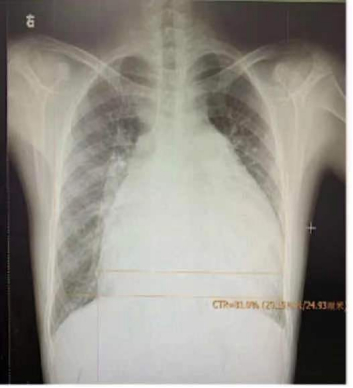

1.胸部X线

图 肺动脉高压患者胸片